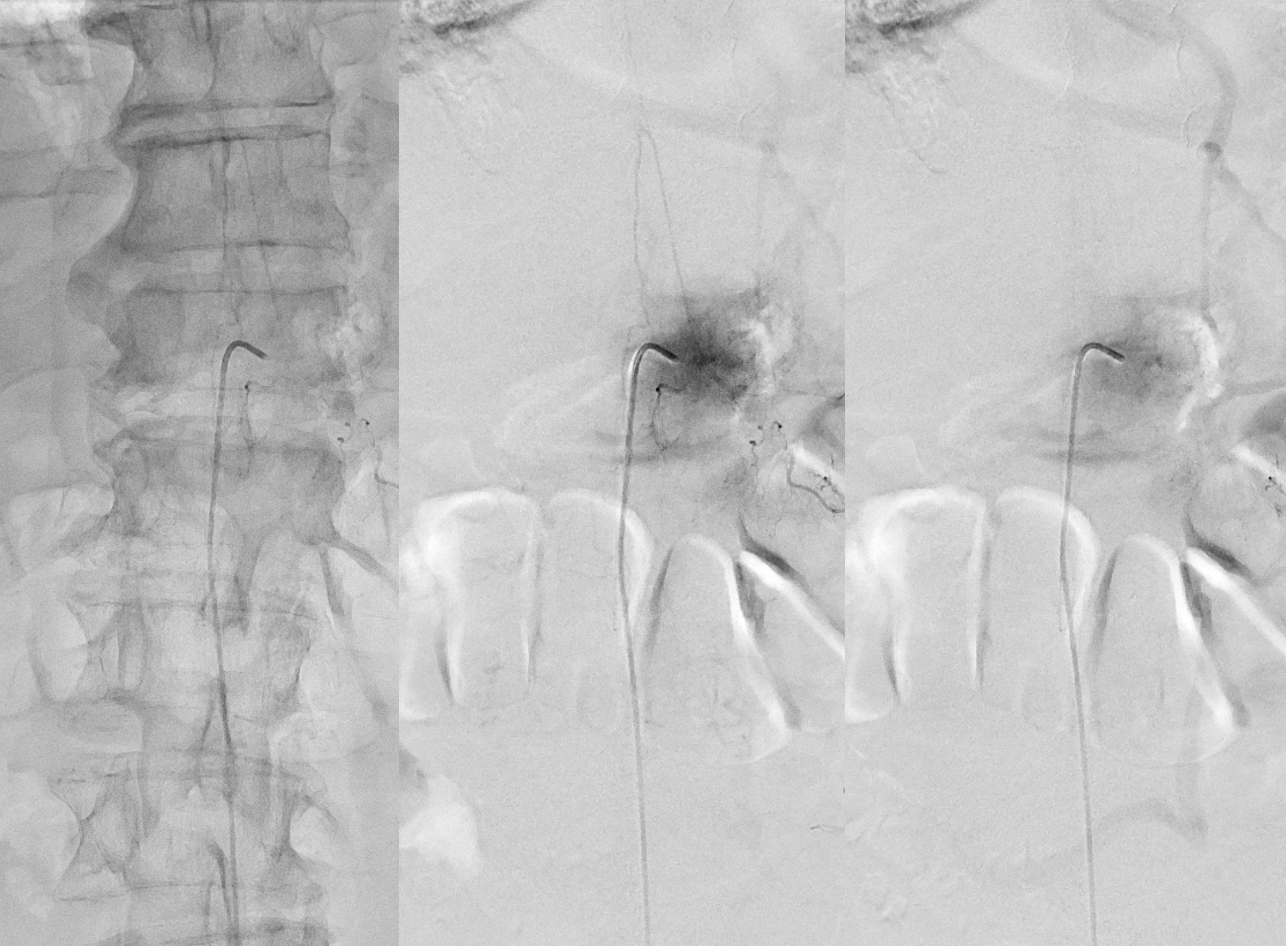

Now to treatment. Hands are raised to get optimal Cone Beam CT view of the fistula (see Cone Beam CT Comprehensive Section, particularly Spinal CBCT Page, on details of how to do this). In this case, we do a dual volume 7 second unbinned “micro” acquisition, with injection of 100% contrast at 1 cc/second for 10 seconds with 3 second delay. Reconstructions are MIP and VR

VR

Headway duo near fistula. There are several other inflows, and the position is not optimal

Below is a better position. The fistula is at the level of the ball of vessels above the microcatheter tip. Several tributaries are present, which is not great, as they will tend to polymerize nBCA before it reaches the vein. Fortunately the radicular venous segment is long, before it reaches cord surface veins, so there is a lot of safety. This is not the case with upper thoracic fistulas, and we don’t want to spill glue into cord surface veins. It promotes thrombosis, which is erroneously known as the Foix-Alajouanine syndrome. The actual syndrome was described by Foix and Alajouanine as the clinical end stage of untreated spinal dural fistulas — ascending paralysis, followed by respiratory dysfunction, aspiration, and death. It was not an iatrogenic problem. The name was adopted to describe post-treatment acute deterioration due to thrombosis of enlarged cord veins after closure of the fistula and reduction of venous flow, in part because clinical presentation is comparably horrible. Typically happens some 6-12 hours after treatment, and almost always within 24 hours. Treatment is with aggressive emergent anticoagulation, and outcome is variable.

A 1:2 nBCA:lipidol dilution was chosen because of additional arterial inflows over which we had limited control (we usually use 1:1). Result seems good

Not so fast. Fistula still alive — which is exceptionally rare after putting this much glue into the vein. Yes, glue is diluted but still its plenty. There is also heparin on board — we pre-treated given massive venous congestion and concern for thrombosis. Still, this is extremely rare. Much slower, but still alive. It is a mistake to hope it thromboses later. Very likely it will not, and hoping it will only contributes to the reputation that endovascular is less effective than surgery.

Re-catheterization (left and center) and additional nBCA injection — even more dilute now that the vein outflow is relatively protected. We think this is good now.

Post. It is important to control from other levels (left T12, left L2, and right L1) — not shown.